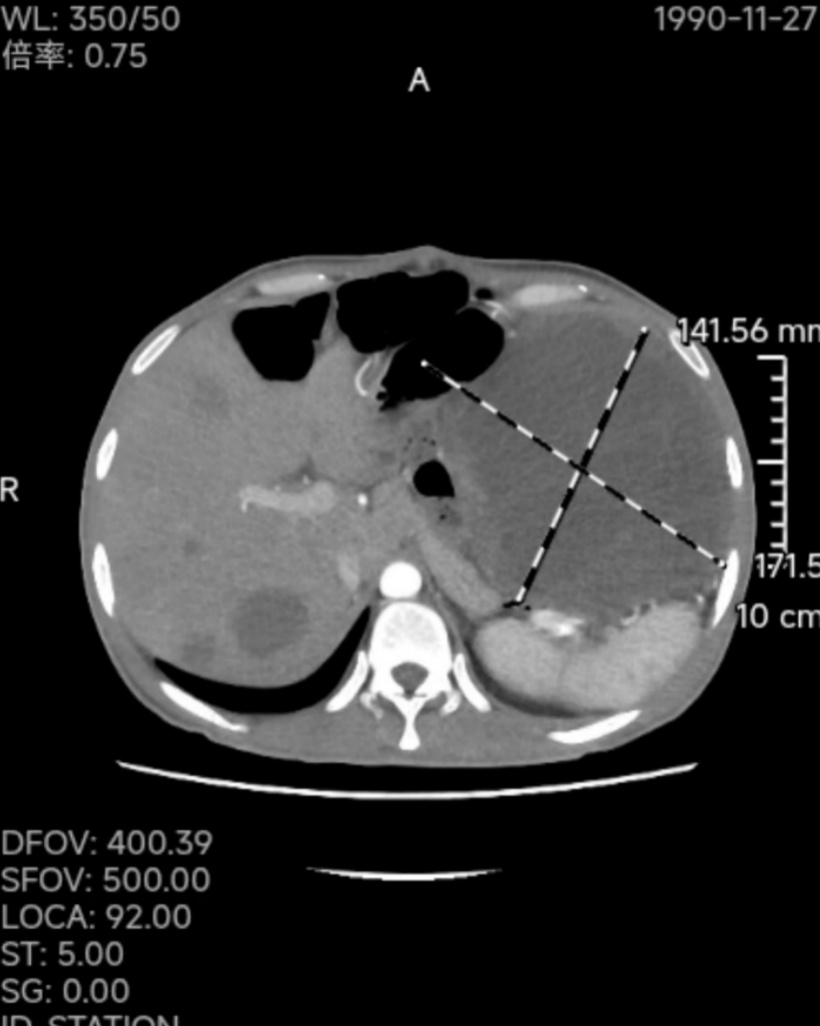

CT检查显示,其腹部存在肿物,考虑为小肠间质瘤复发,且已压迫腹腔脏器,胃肠肛肠外科主任邱磊介绍,若不及时干预,王先生可能出现失血性休克甚至呼吸心跳骤停。

为挽救王先生生命,医院迅速制定手术方案,并启动多学科联动。经过7个半小时的手术,医生成功取出 5枚巨大肿瘤,其中最大直径达 20公分,并抽取脓性液体约 1000ml,总重量达 20斤。